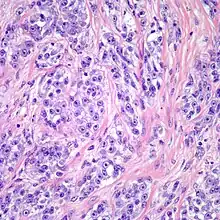

| Clear cell sarcoma. Tumor cells with prominent nucleoli and clear cytoplasm are arranged in well-defined nests surrounded by dense fibrous stroma. | |

Despite the name clear cell sarcoma, the tumor cells do not necessarily need to have clear cytoplasm. The lesion has a distinctly nested growth pattern with a mixture of spindle, epithelioid and tumor giant cells. Approximately two thirds of the tumors contain melanin pigment. Clear cell sarcoma, similar to melanoma, has consistent positivity for S-100, HMB-45, and MITF.[6]